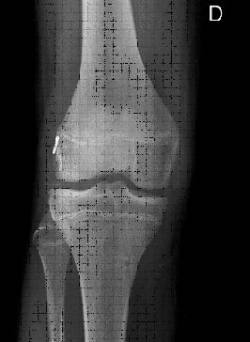

Els tractaments convencionals descrits per a la reparació del lligament creuat anterior poden provocar efectes iatrogènics sobre el cartílag de creixement.

El factor determinant en la possibilitat de l’aparició d’aquests efectes adversos no és l’edat cronològica del pacient, sinó el seu estadi maduratiu (estadis de Tanner <II determinats per l’aparició de caràcters sexuals secundaris).

També estan involucrats en la possibilitat de lesionar el cartílag de creixement el tipus d’empelt utilitzat (amb pastilles òssies), una excessiva tensió d’aquest a l’hora d’implantar-lo i el diàmetre de les tunelitzacions emprades.

S’evita el dany del cartílag de creixement mitjançant l’ús de tunelitzacions retrògrades (sistema de retroconstrucció) que ens permet restituir la funcionalitat de l’articulació sense afectar el cartílag de creixement i mantenint la isometria de l’empelt implantat.